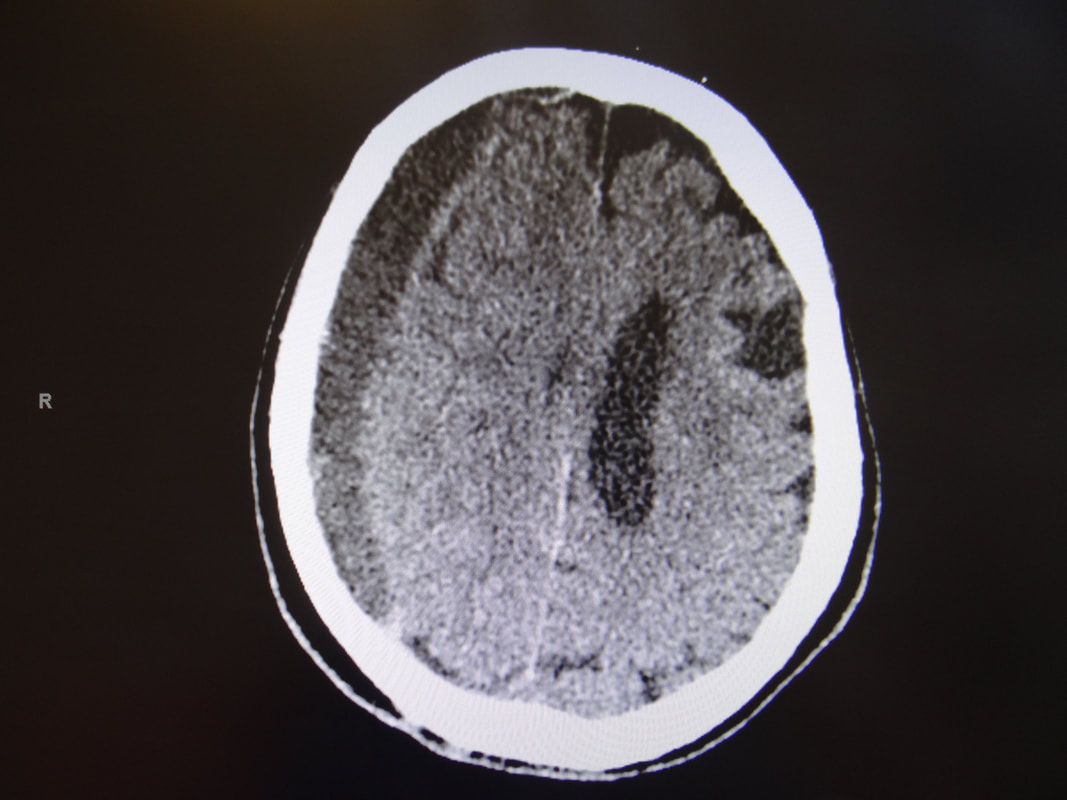

C’est l’augmentation du liquide céphalorachidien (LCR) dans le cerveau. En effet, le cerveau produit ce liquide, qui s’écoule dans des cavités du cerveau pour ensuite passer au niveau de la moelle épinière, et rejoindre à nouveau le cerveau où il est résorbé. Il arrive parfois que l’écoulement soit obstrué (par une tumeur, par exemple) ou que le système d’évacuation est bloqué (par un saignement ou une infection). Dans ces situations, le liquide s’accumule dans le cerveau provoquant une hydrocéphalie.

Le traitement de l’hydrocéphalie consiste à placer un drain (drain ventriculo-péritonéal) dans une cavité du cerveau (ventricule) et le connecter dans l’abdomen (cavité péritonéale).

Un saignement peut arriver dans différentes parties du cerveau. En effet, on distingue plusieurs types d’hémorragies cérébrales :

1. L’hémorragie sous arachnoïdienne, c’est un saignement dans les méninges (espace sous-arachnoïdien). La cause la plus fréquente est une rupture d’anévrisme ou une malformation vasculaire (malformation artérioveineuse, fistule durale).

2. L’hémorragie sous durale se situe entre le cerveau et les méninges. Il existe trois types : l’hématome sous dural aigu, sub-aigu et chronique, dépendant du temps. La cause la plus fréquente est le traumatisme crânien. L’hémorragie aiguë est une urgence neurochirurgicale, car le sang provoque un effet de masse sur le cerveau pouvant aboutir au coma et à la mort.

3. L’hémorragie intracérébrale correspond à un saignement dans le parenchyme du cerveau. Il existe de nombreuses causes, comme l’hypertension artérielle, les malformations vasculaires, les tumeurs,…

Le traitement de ces hémorragies consiste à faire une craniotomie (trépanation) pour pouvoir évacuer le sang. Dans le cas des anévrismes ou des diverses malformations vasculaires, le traitement consiste en un clippage de l’anévrisme ou une embolisation par voie endovasculaire (via les vaisseaux sanguins).